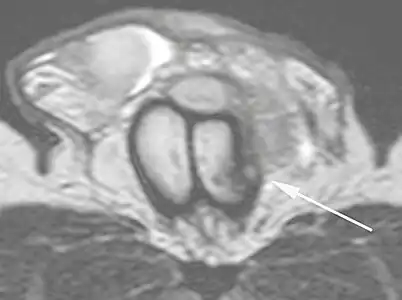

Figure 4 A: Ultrasound of the penis, right lateral view. Longitudinal section showing rupture of the tunica albuginea with an adjacent 1.92 cm hematoma (between calipers), due to trauma.[2] -

B: Axial T2-weighted turbo spin-echo magnetic resonance imaging scan showing left-sided discontinuity of the tunica albuginea (arrow), secondary to fracture.[2]